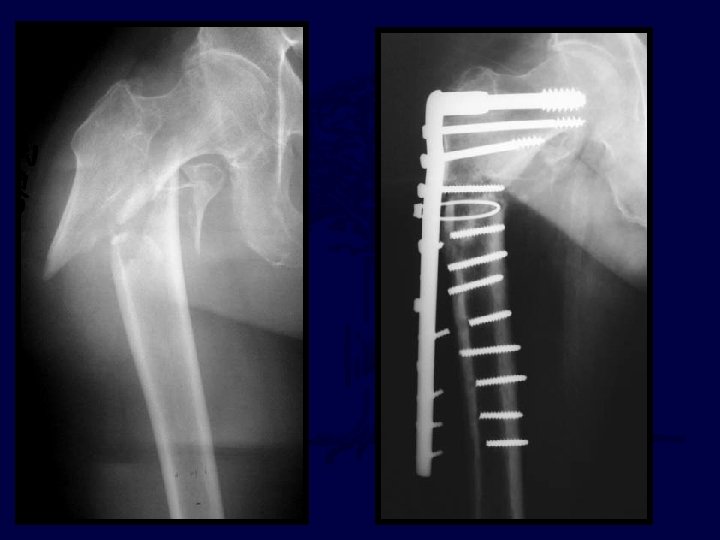

71 yo renal txplnt pt c CHF What to do? ?

If my patient, I would use: 1. Hip screw and sideplate 2. Hip screw and IM nail (TFN) 3. Reconstruction Nail (2 proximal medullary-cephalic screws) 4. Blade Plate 5. Other

percutaneous reduction

Uneventful Healing, WBAT 6 wks 12 wks